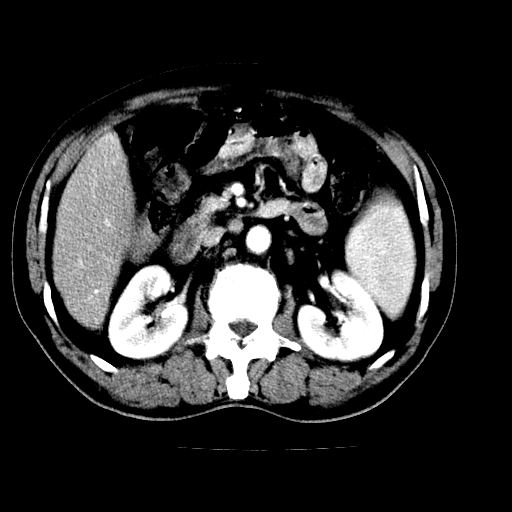

男,66岁,上腹部不适、黄染一周。彩超示:肝左叶占位,肝内胆管扩张,胆总管扩张,胆总管占位?

肝左叶占位性病变,并胆管扩张,符合胆管细胞癌ct表现,门脉左支受累,左肾囊肿。窗宽太窄了,其他的看不清

左叶胆管细胞癌累及胆总管,门脉左支受侵,慢性胆囊炎胆结石,左肾小囊肿